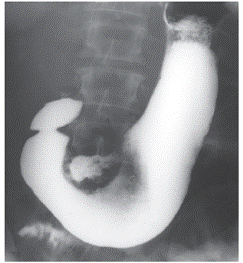

Рис. 2. Пациент К., 65 лет: рентгеноскопия желудка (контрастирование бариевой взвесью). Обзорная рентгенограмма желудка и двенадцатиперстной кишки в прямой проекции. Чашеобразный рак по малой кривизне антрального отдела желудка без нарушения эвакуации